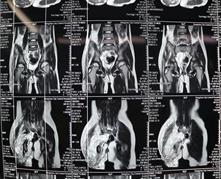

经过检查发现小诺右侧臀部及大腿有大面积的淋巴畸形,右小腿、右足踝部及右足底也有许多弥散性的肿块,不仅病变部位多且侵犯严重,加上之前已经做过三次手术,这次的手术对于医生而言无疑是巨大的挑战!经过前期充分的准备,小诺的手术如期进行,从上午10点50一直到晚上11点,历时整整12个小时,终于顺利完成手术,术中发现病变累及大面积的正常肌肉和多处神经,乔主任巧妙的采用切除和微创相结合的方式治疗病变部位,仔细分离重要的血管和神经,将大面积的病变全都切除。术后小诺身体恢复情况很好,目前正在一步步的康复,迎接她的是健康和快乐的明天!